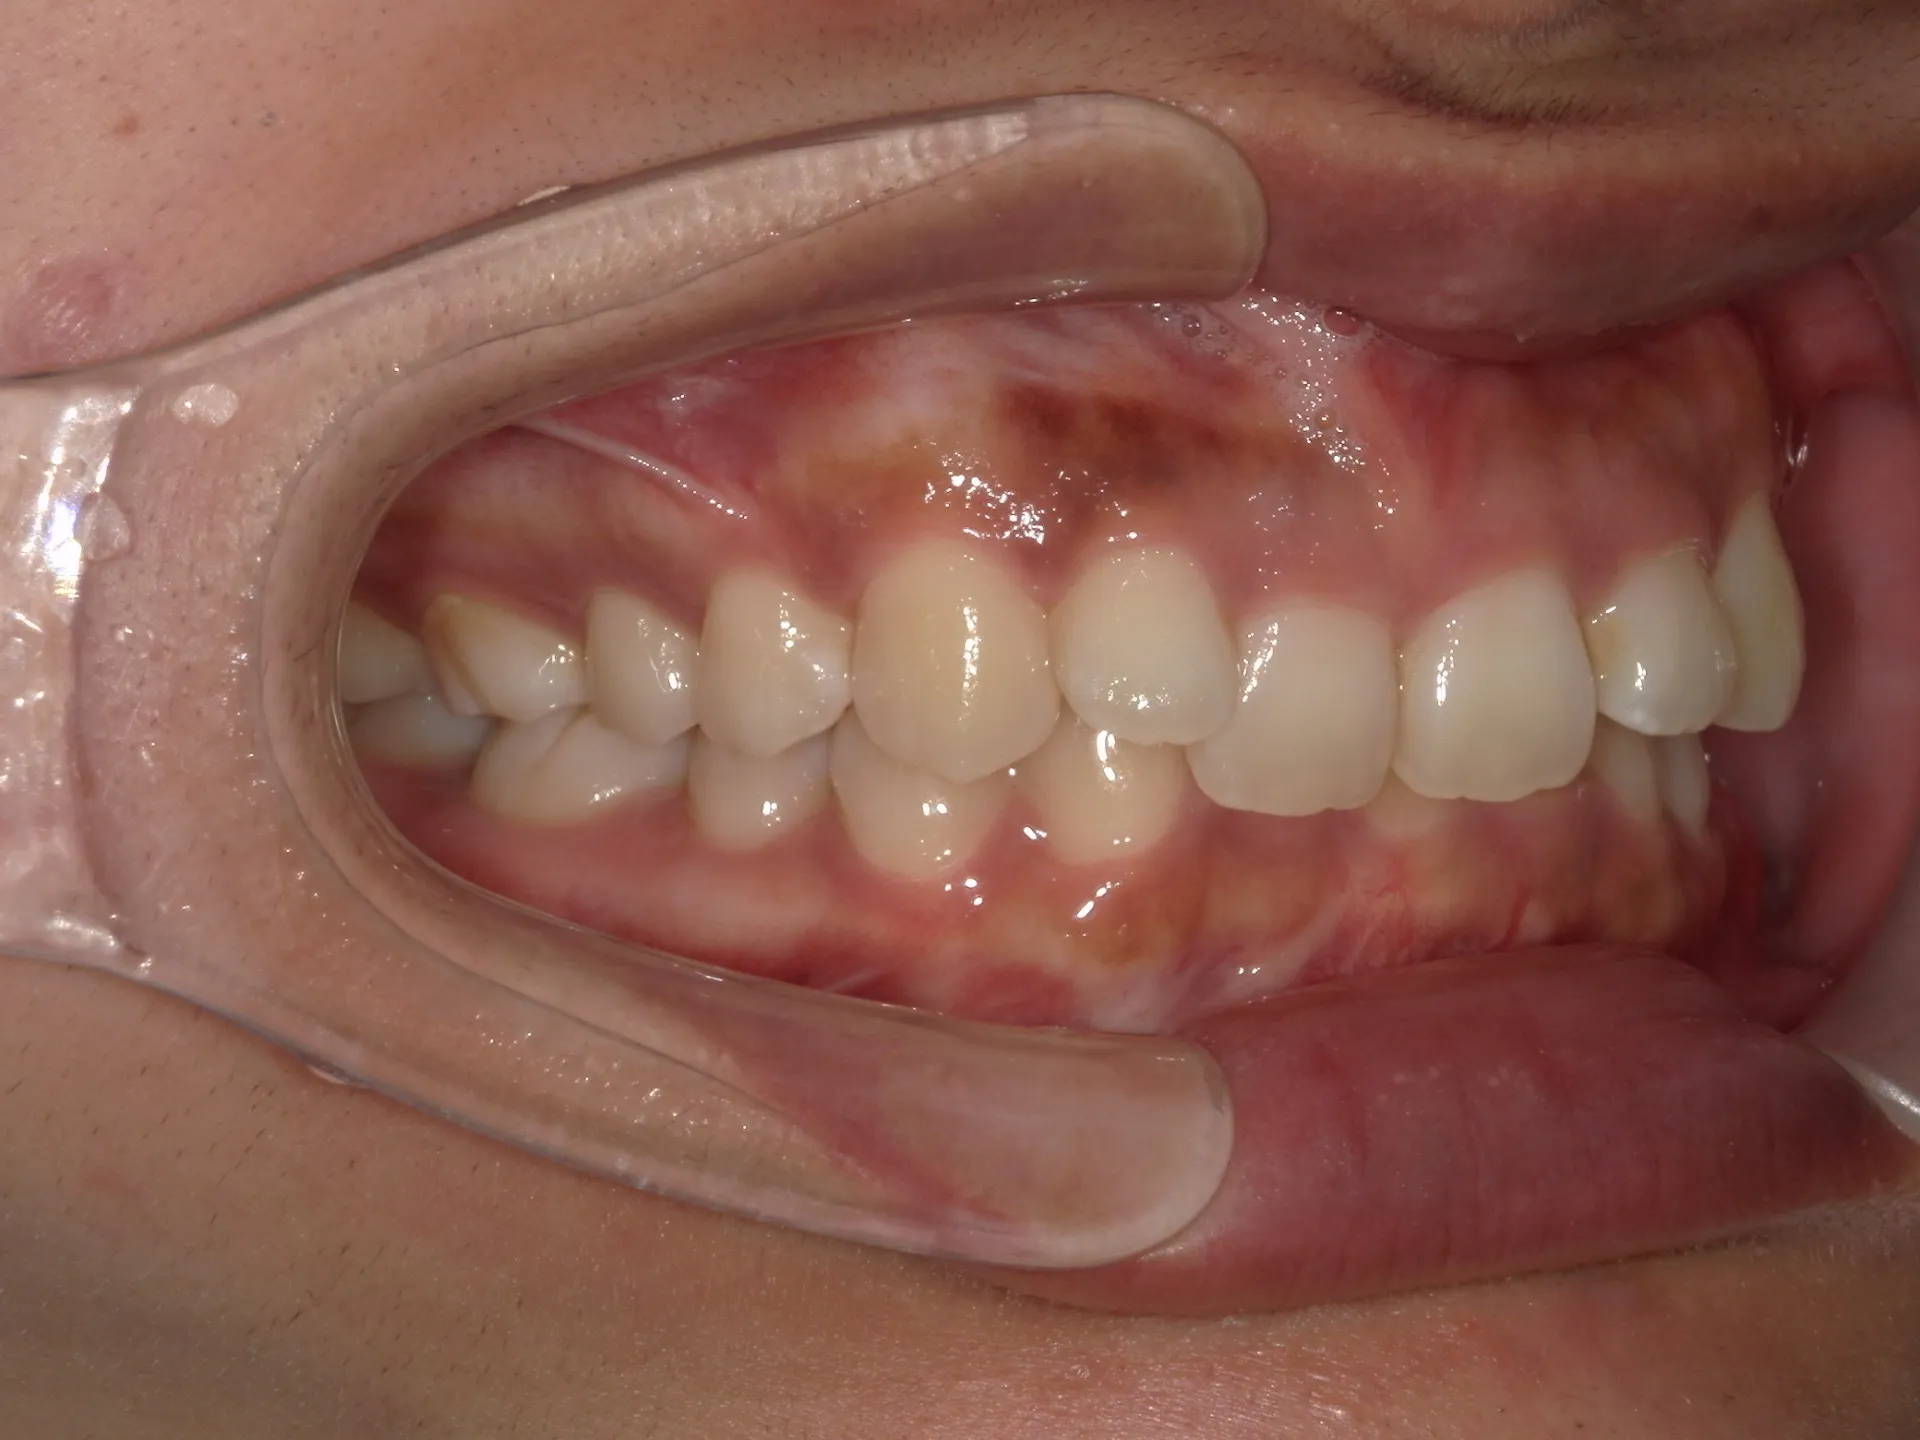

前歯が内側に倒れてたりしませんか?

または2番目の歯が外側に飛び出していませんか?

この2つはよく同時に起こることがあります。

今回はインビザライン矯正治療(マウスピース矯正)で治療した症例についてご紹介いたします。